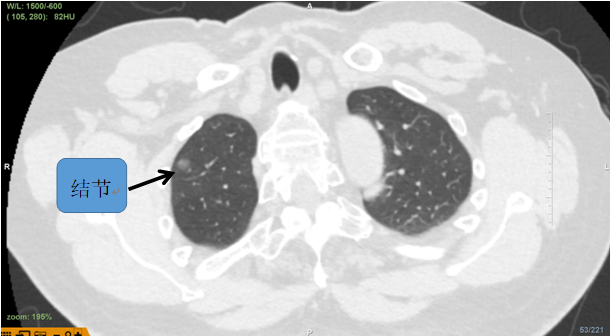

陈女士今年59岁,入住我院胸部外科二区,胸部CT提示右肺上叶尖段可见一磨玻璃结节,大小约9.5mm,考虑恶性可能性大,需手术切除。

该病灶于右肺上叶尖段可见一磨玻璃结节,结节较小,且位置极高,常规器械滑行或手指触摸定位结节难度较大,为达到精准定位、精准治疗,且有效缩短患者手术时间目的。朱坤寿主任医师及林绍峰副主任医师术前充分讨论,利用Lungpro增强现实支气管导航术前三维重建支气管树,分析病灶与气道位置关系,拟定染色标记胸膜区域。

患者CT图